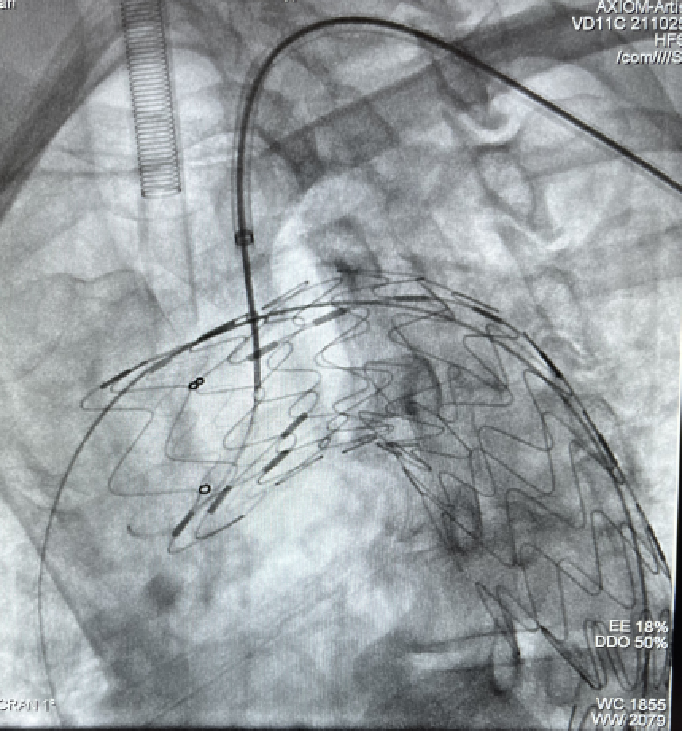

case 2

患者男性,78岁,胸主动脉瘤,采用双开窗技术(LSA+LCCA)重建分支。Futhrough系统在直径较小的血管中(成角小、行程长)实现精准穿刺,术后12个月随访显示支架通畅,无内漏或移位。